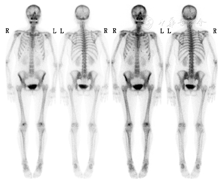

PTH依赖性高钙血症的病因包括:原发性甲状旁腺功能亢进症、三发性甲状旁腺功能亢进症、异位肿瘤分泌PTH。患者无慢性肾功能不全和继发性甲状旁腺功能亢进症病史,而异位肿瘤分泌PTH罕见,因此首先考虑原发性甲状旁腺功能亢进症。原发性甲状旁腺功能亢进症为甲状旁腺腺瘤、增生或腺癌导致甲状旁腺自主分泌PTH,进而使血钙升高引起临床症状。该例患者头颅侧位及双手正位片提示骨质疏松,99Tcm-亚甲基二膦酸盐(methylene diphosponate, MDP)全身骨显像(德国Siemens E.CAM SPECT/CT;图1)见全身骨骼摄取普遍轻度增高,软组织本底摄取降低,符合代谢性骨病的超级骨显像表现。